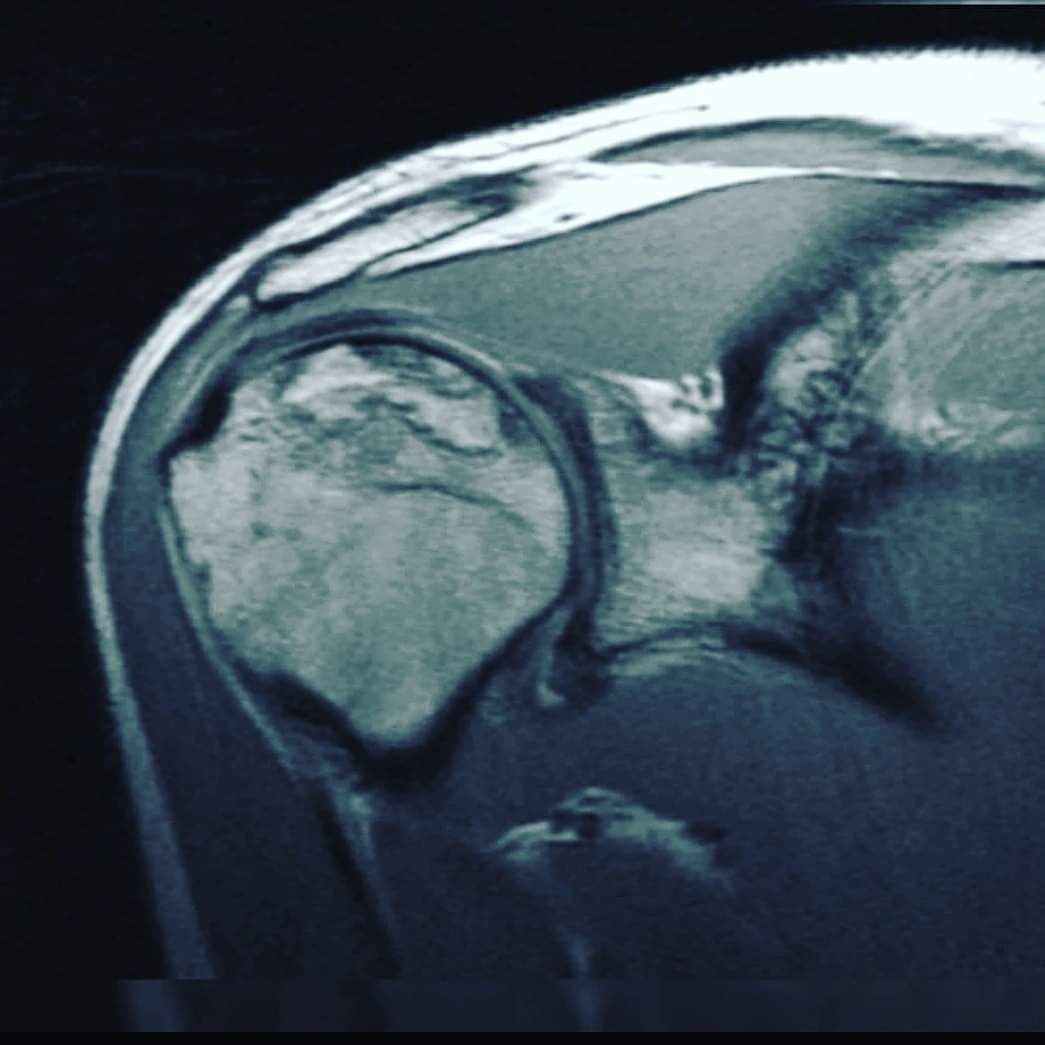

На цьому знімку плечового суглоба – деформація кісткової частини 4 ступіню. Зарадити нічим вже не можна. Не чекайте цього! Виправити, відновити, покращити функцію суглоба, хребта, враженого навантаженнями, чи віковими змінами, пов’язаними зі старінням – МОЖЛИВО! Гарна новина в тому, що Ви, при наявності будь-яких проблем с хребтом та суглобами, маєте змогу зараз, вчасно звернутись до лікаря-фахівця, який зупинить незворотні зміни. Запропонує метод відновлення, який, без перебільшення може врятувати Ваш хребет, чи суглоб, від заміни хірургом на штучний…